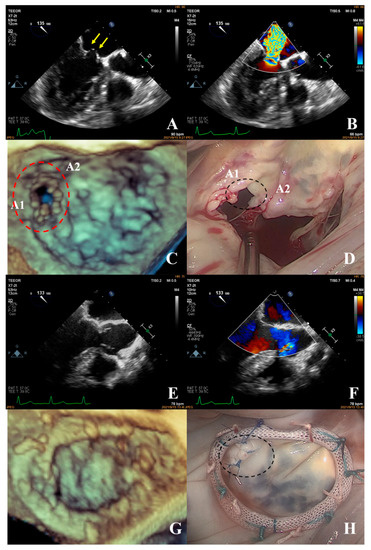

Prediction of Surgical Approach in Mitral Valve Disease by XGBoost Algorithm Based on Echocardiographic Features

In this study, we aimed to develop a prediction model to assist surgeons in choosing an appropriate surgical approach for mitral valve disease patients. We retrospectively analyzed a total of 143 patients who underwent surgery for mitral valve disease. The XGBoost algorithm was [...] Read more.

In this study, we aimed to develop a prediction model to assist surgeons in choosing an appropriate surgical approach for mitral valve disease patients. We retrospectively analyzed a total of 143 patients who underwent surgery for mitral valve disease. The XGBoost algorithm was used to establish a predictive model to decide a surgical approach (mitral valve repair or replacement) based on the echocardiographic features of the mitral valve apparatus, such as leaflets, the annulus, and sub-valvular structures. The results showed that the accuracy of the predictive model was 81.09% in predicting the appropriate surgical approach based on the patient’s preoperative echocardiography. The result of the predictive model was superior to the traditional complexity score (81.09% vs. 75%). Additionally, the predictive model showed that the three main factors affecting the choice of surgical approach were leaflet restriction, calcification of the leaflet, and perforation or cleft of the leaflet. We developed a novel predictive model using the XGBoost algorithm based on echocardiographic features to assist surgeons in choosing an appropriate surgical approach for patients with mitral valve disease. Full article